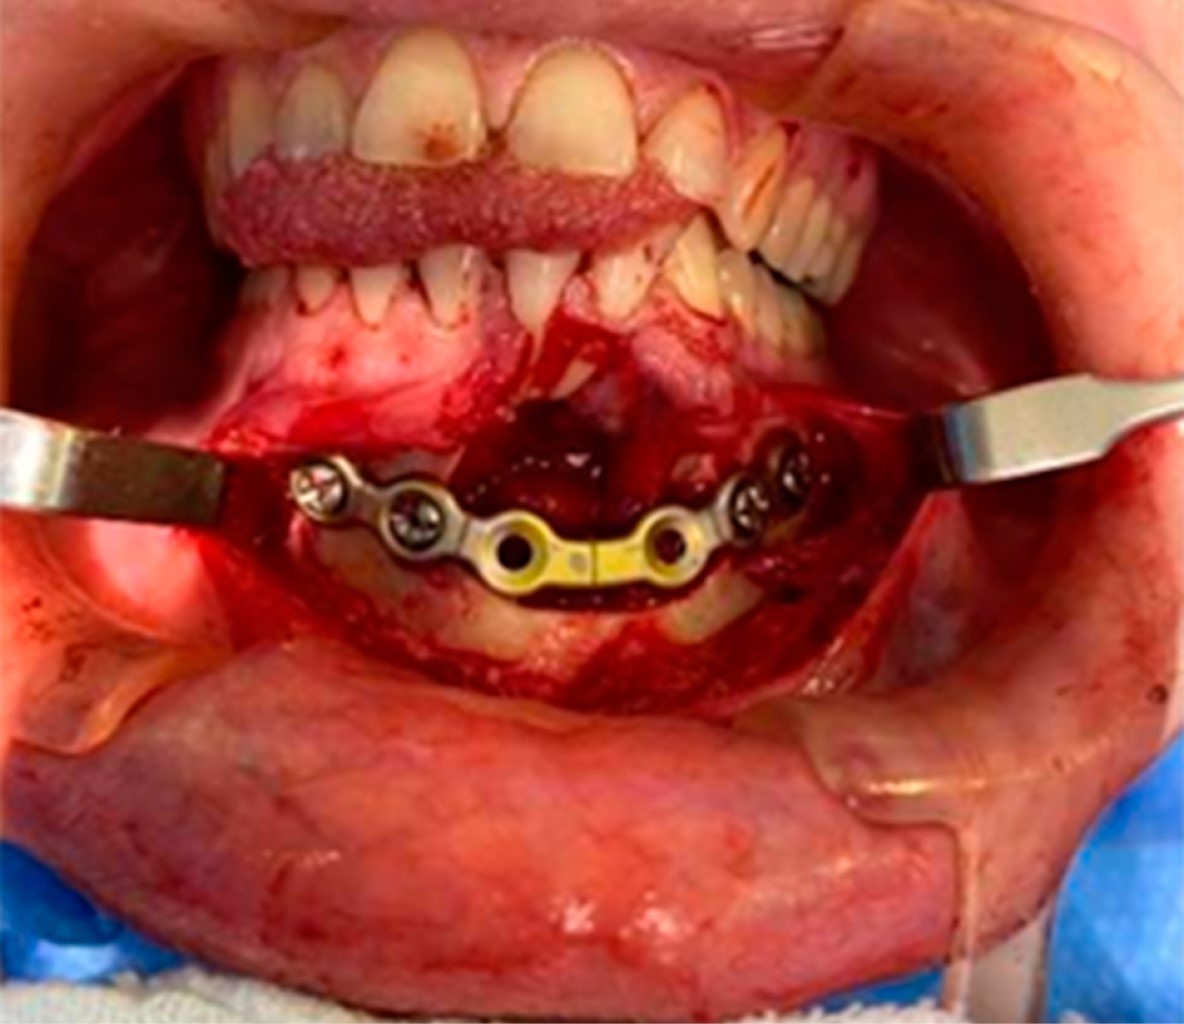

Se optó por una fijación interna estable con una placa de reconstrucción Stryker® de tipo 2,4 con el fin de prevenir el riesgo de fractura patológica en el postoperatorio, debido a la fragilidad ósea de la cortical lingual, y porque la lesión se encuentra en el arco central mandibular, generando fragilidad a la región debido a las fuerzas musculares vectoriales y a la torsión (Figura 5).